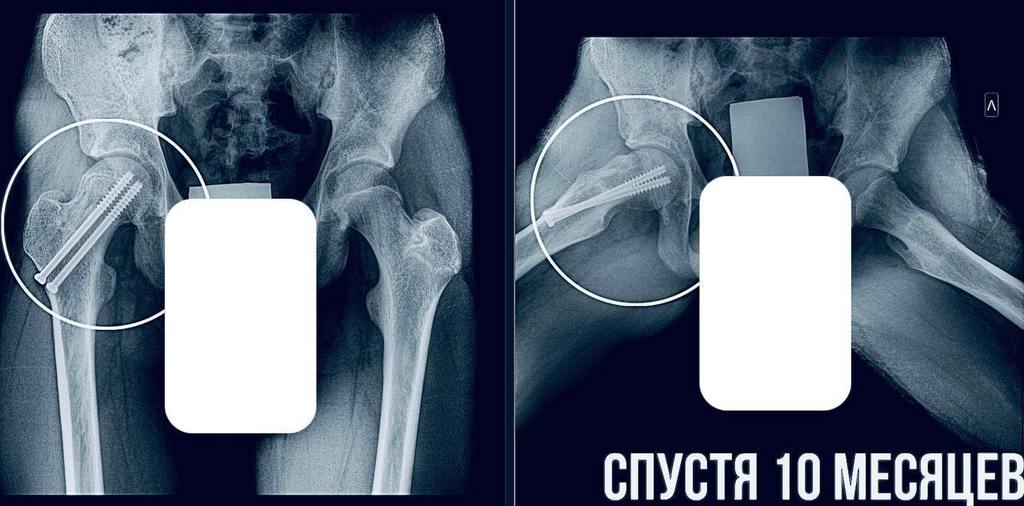

— Пациенту требовалась срочная операция. Мы выполнили фиксацию сустава, чтобы остановить смещение и дать ему возможность правильно развиваться. Это убережет юношу от раннего артроза и ограничений подвижности в будущем, — отметил главный врач МОДКТОБ Александр Григорьев.

На данный момент пациент идет на поправку, в ближайшее время его выпишут домой, после чего он начнет курс реабилитации.